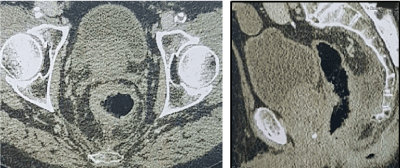

The case was an 84-year-old patient with stage IV obliterative arteriopathy of the lower limbs (aortobifemoral prosthesis) and ischemic cardiopathy (quadruple bypass), who was taking an antiplatelet drug. A rectal tumour was diagnosed in the context of rectal bleeding in February 2006. An investigation discovered a middle-low rectal Lieberkuhnian hemicircumferential adenocarcinoma, extending 50 cm from the anal margin with locoregional extension to inguinal lymph nodes and mesorectum (Figure 1). He did not present with an altered general condition and was performance status 1. His major symptom was daily rectal bleeding causing chronic symptomatic anaemia. He had received several argon plasma coagulation treatments between February 2006 and April 2007. Palliative external-beam radiotherapy was based on the persistence of symptomatic anaemia due to bleeding. Radiotherapy was delivered on the rectal volume, and the prescribed dose was 60 Gy in 30 fractions over 47 days between July and September 2007. The 1-month clinical examination revealed a two-thirds reduction in the tumour and a complete abolition of rectorragy. He did not complain of pelvic pain and walking was undisturbed. His main handicap was related to arteriopathy. In February 2008, the patient started to complain of severe perineal pain, justifying the prescription of strong opioids: 10 mg morphine and 100 µg/hour fentanyl patch with nefopam. An abdominopelvic scan showed that the rectal tumour was stable (Figure 2). In June 2008, his general condition had worsened to performance status 3. He described urinary and anal incontinence, and strong opioids were insufficient. In addition, rectal bleeding had begun, with the tumour exteriorised in the anal canal.

Figure 2. Abdominopelvic scan.